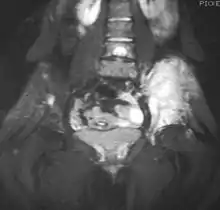

![]() ![]() | |

| Top: Ewing sarcoma of the thigh bone on a child's CT scan Bottom: Extraskeletal Ewing sarcoma of the hard palate | |